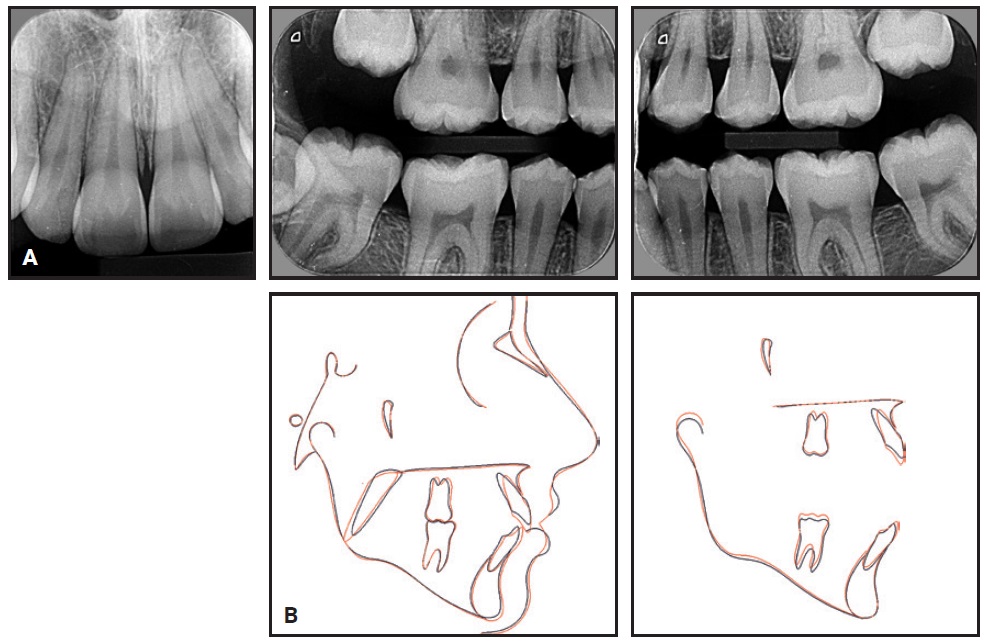

Fig. 6 13-year-old female patient with bilateral Class I molar relationship, anterior open bite, moderate lower anterior crowding, and excessive overjet before treatment (continued in next image).

Clinical examination confirmed an anterior open bite extending from first premolar to first premolar, a bilateral Class I molar relationship, moderate lower anterior crowding, and excessive overjet. The panoramic radiograph revealed the presence of unerupted upper second and lower third molars and agenesis of the upper third molars. The upper second molars were favorably positioned for later eruption,36 with incomplete rhizogenesis (Fig. 6B). There was no deviation between centric occlusion and centric relation, and there were no signs of TMD. Cephalometric analysis found an anteroposterior maxillomandibular discrepancy with mandibular deficiency, a slightly vertical growth pattern with an excessive mandibular-plane angle, and a convex skeletal profile. The upper incisors were slightly protrusive, but the lower incisors were well positioned.

Fig. 6 (cont.) 13-year-old female patient with bilateral Class I molar relationship, anterior open bite, moderate lower anterior crowding, and excessive overjet before treatment.